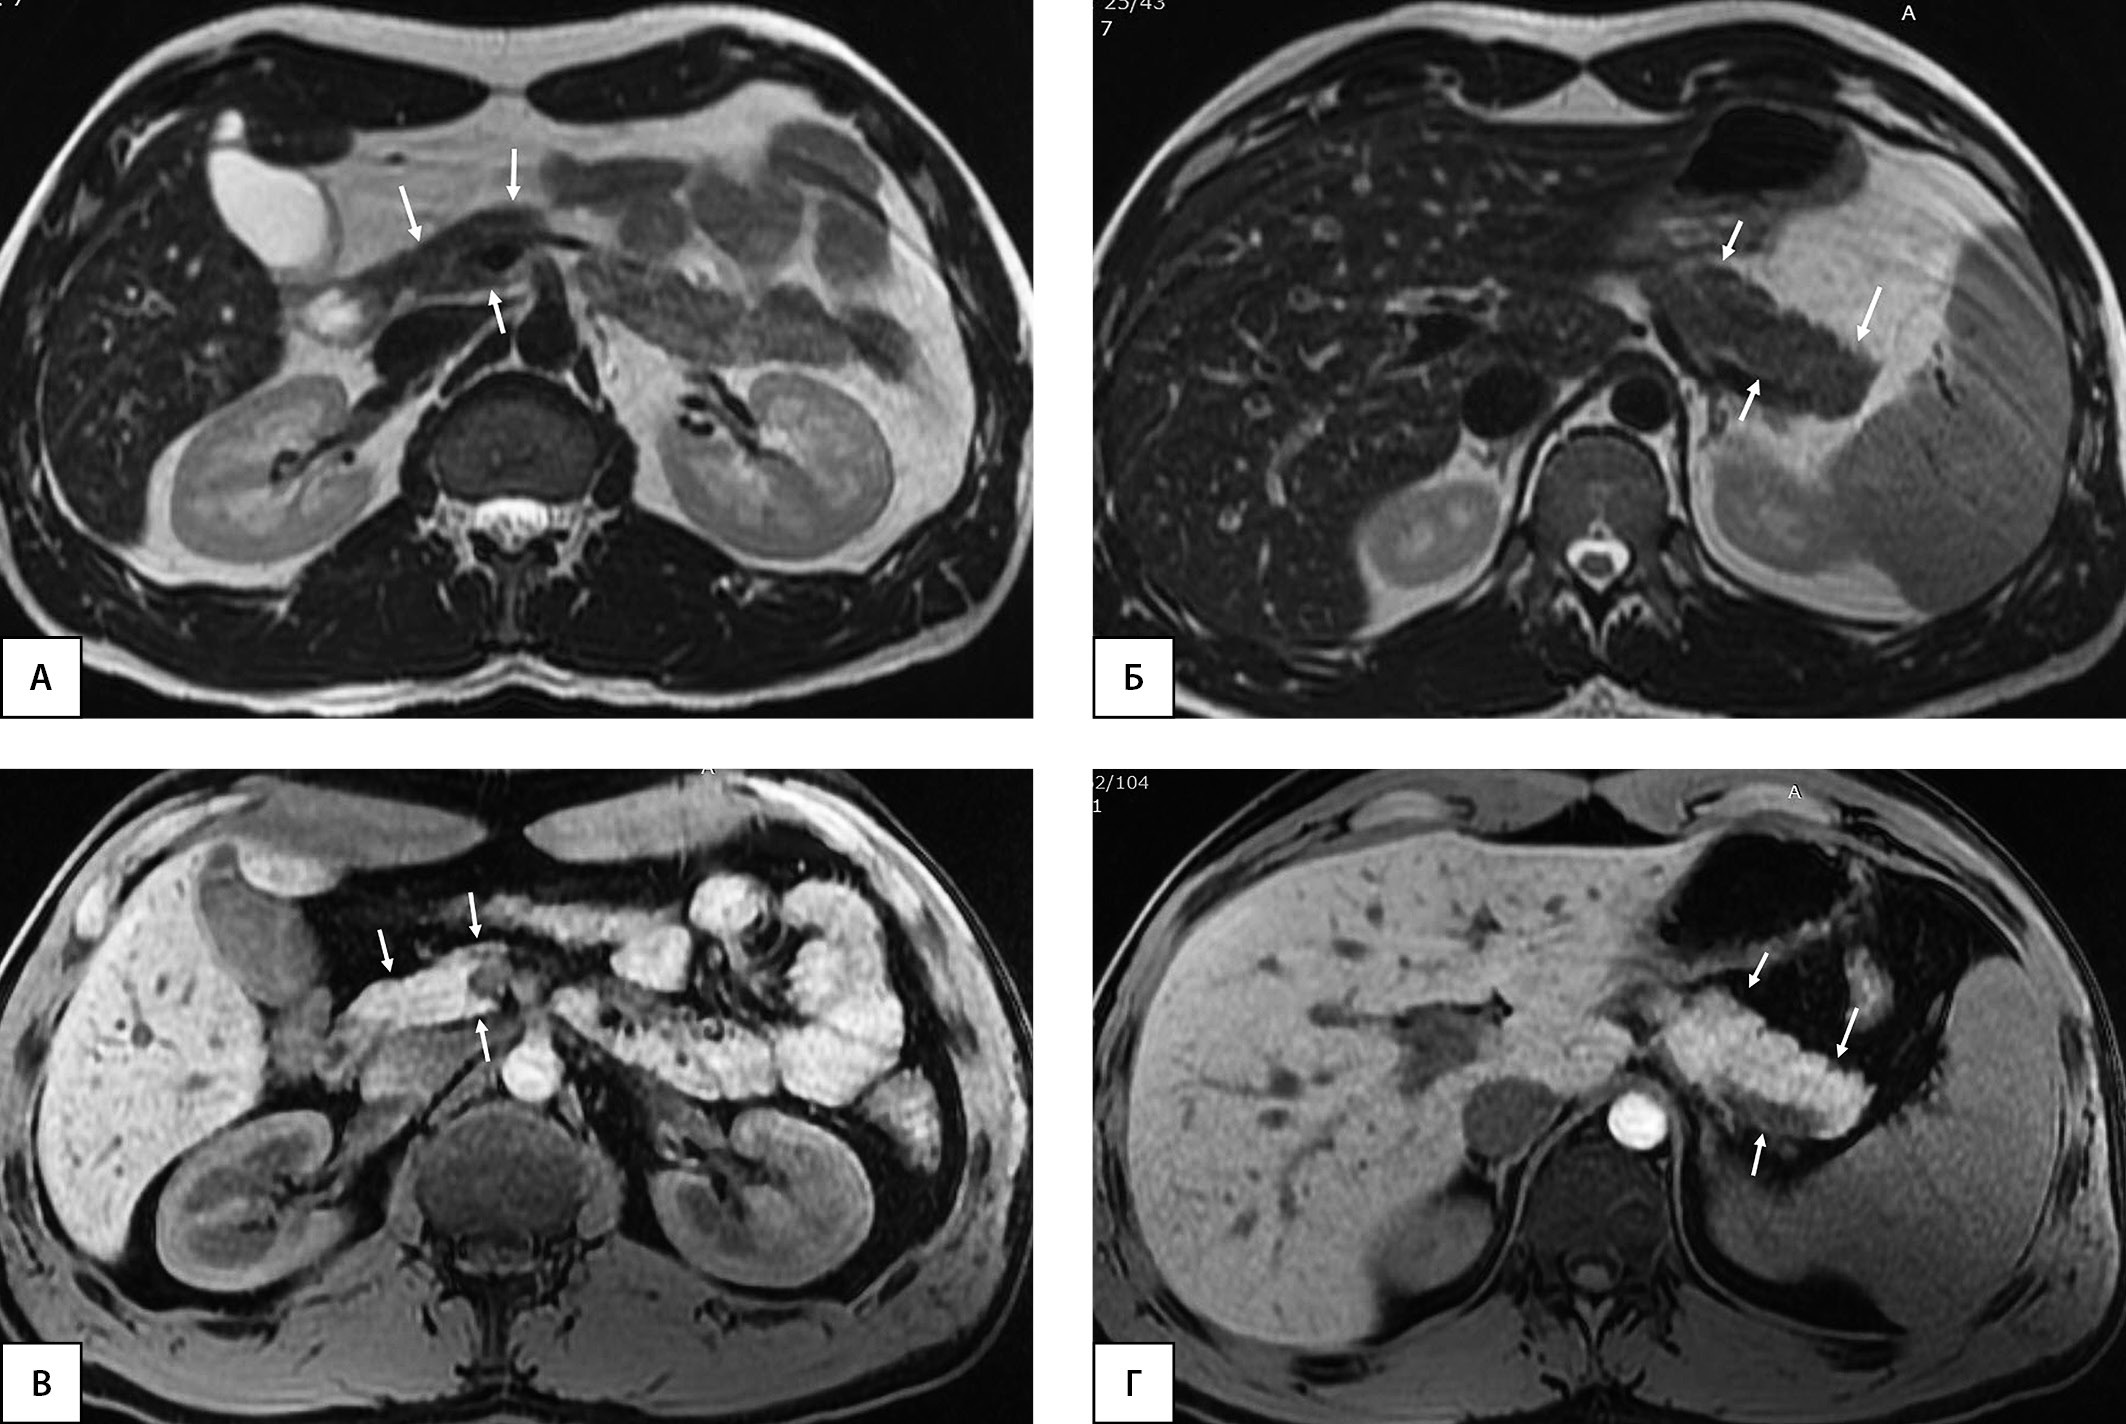

Рисунок 3. Пациент, 24 года (длительность СД1 4 года). МРТ органов брюшной полости на уровне головки поджелудочной железы (А, В) и на уровне тела и хвоста (Б, Г). А, Б — Т2-ВИ, аксиальная плоскость; В, Г — Т1-ВИ, аксиальная плоскость. Определяется диффузное снижение объема поджелудочной железы, больше изменения выражены на уровне головки (стрелки). ОПЖ=38,1 мл; ОПЖ/ИМТ=38,1/23,4=1,63 мл/(кг/м2); ОПЖ/ППТ=38,1/1,94=19,64 мл/м2.

Примечание. ОПЖ — объем поджелудочной железы. ИМТ — индекс массы тела. ППТ — площадь поверхности тела. ВИ — взвешенные изображения.